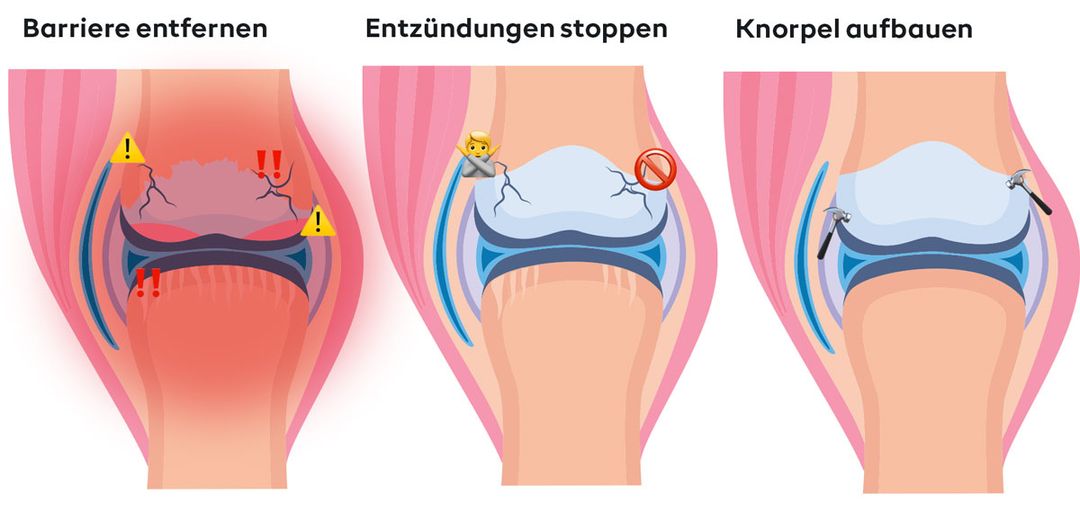

Dit zijn de drie cruciale stappen:

Stop ontstekingen – de brand in je gewrichten

Hormonale schommelingen bevorderen chronische ontstekingen, waardoor het kraakbeen letterlijk wordt aangetast. Het natuurlijke actieve ingrediënt boswellia, in de vorm van AKBA-boswellinezuur, heeft een gerichte ontstekingsremmende werking en beschermt je kraakbeen, in plaats van het te beschadigen zoals veel pijnstillers.

Zonder ontstekingsremmende maatregelen kan je lichaam de afvalbarrière niet afbreken en blijven alle andere maatregelen ineffectief.

Het doorbreken van de afvalbarrière – de sleutel tot genezing

Tijdens de menopauze hopen afvalstoffen zich op in de gewrichten doordat de bloedsomloop en lymfestroom verstoord zijn. OPC (druivenpitextract) verbetert de bloedsomloop, breekt deze barrière af en levert verse voedingsstoffen daar waar ze nodig zijn.

Bovendien worden ontstekingsafvalproducten verwijderd en wordt de weg vrijgemaakt voor belangrijke voedingsstoffen.

Kraakbeen opnieuw opbouwen – de basis voor mobiliteit

Je kraakbeen kan alleen regenereren als het de juiste bouwstenen krijgt. Silicium uit bamboe-extract levert deze essentiële stoffen en activeert de lichaamseigen kraakbeenproductie.

Maar alleen als de ontsteking wordt gestopt en de barrières worden verbroken, kan het kraakbeen worden herbouwd. Dit is de sleutel op lange termijn tot gezonde, veerkrachtige gewrichten.

Deze drie stappen zorgen er samen voor dat de gewrichtsdetox-methode uniek is.

Het is de eerste aanpak die de grondoorzaken van je problemen aanpakt – precies daar waar conventionele oplossingen falen.